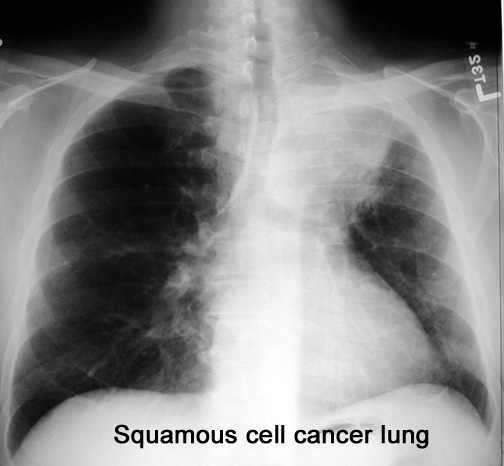

Case 3 Labeled Image What is the differential for thick walled cavity?